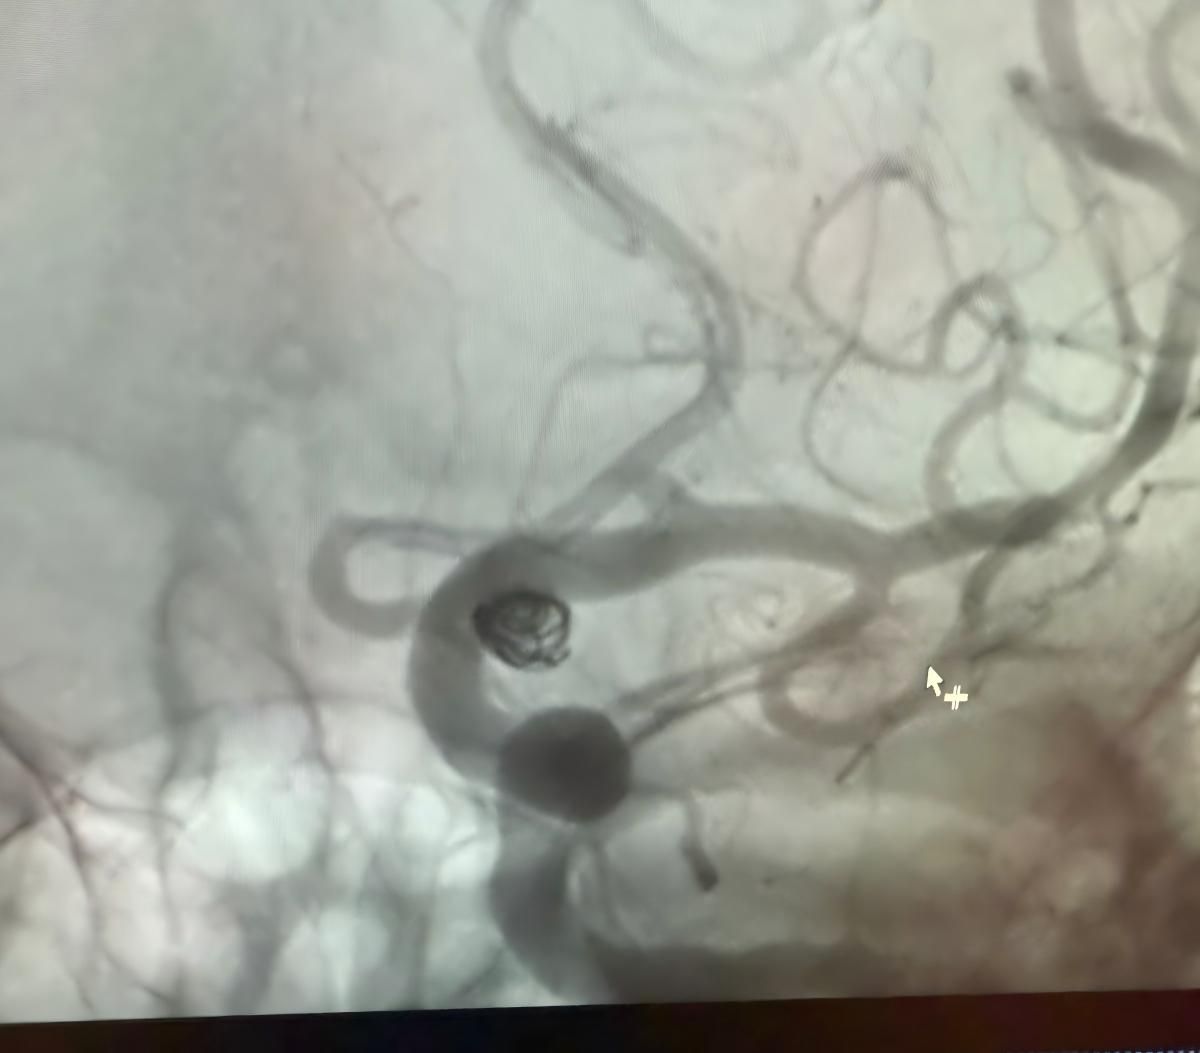

Nous sommes heureux de partager une récente procédure réussie à la Clínica Alma Mater, Medellín, réalisée par le Dr Jorge Mutis.

Le traitement a utilisé le Nuva®Déverseur d'écoulement (TJED-D 5.0-14), Perdenser®Bobine 3D, et Frepass®Microcathéter (TJMC18 Plus) pour un anévrisme de l'artère communicante postérieure.

Le Dr Mutis a souligné l'excellente visibilité de l'appareil et a noté que la récupération était fluide. Il s'est dit très satisfait du résultat final.